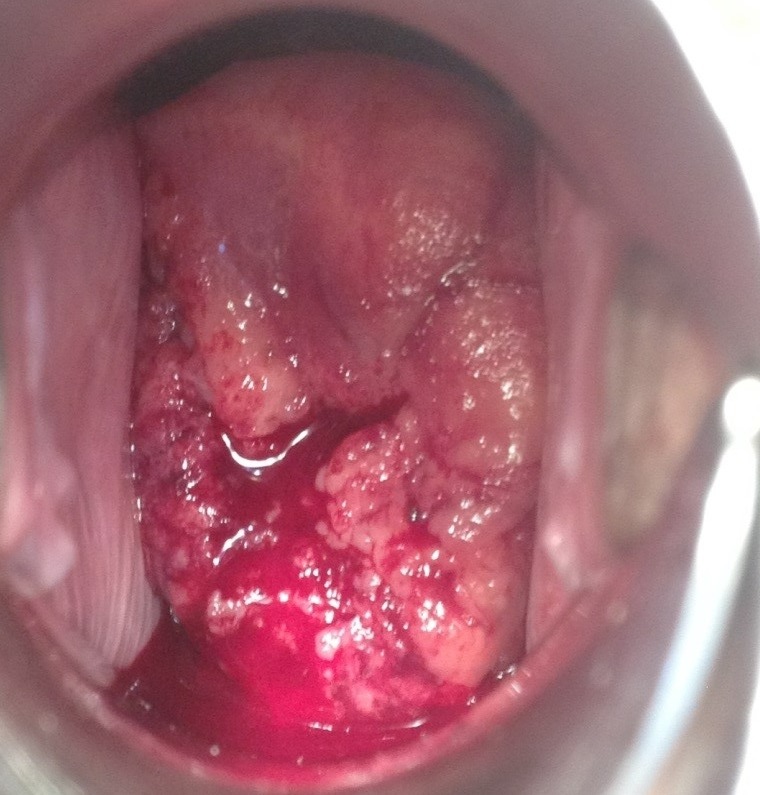

Рис. 2 Опухоль шейки матки

Основными признаками опухоли шейки матки являются:

- кровянистые выделения из половых путей, часто усиливающиеся после полового контакта

- изменения характера и длительности менструации

- боли внизу живота, с иррадиацией в спину и заднюю поверхность бедра.

При запущенных стадиях возможно прорастание опухоли в близлежащие органы — прямую кишку, мочевой пузырь, сдавление мочеточников с нарушением отхождения мочи и появлением болей в области почек. Поэтому ежегодный осмотр онкогинеколога своевременно позволит верифицировать патологический процесс и выполнить весь комплекс необходимых диагностических манипуляций.

Рак шейки матки относится к опухолям визуальной локализации.